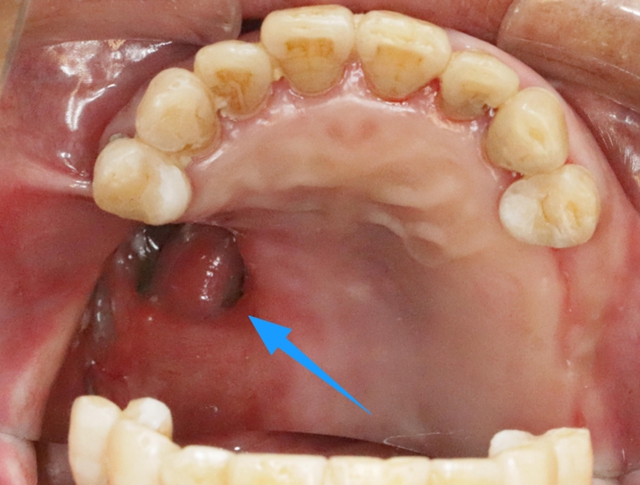

5年前,39岁的彭女士感冒后到当地诊所购买了感冒药,服用后突然出现了双耳听力下降,距离稍微远一点的声音都是模糊的,右耳还伴有耳鸣、持续性电流音,甚至不能与人进行正常的交流。家人赶紧把她带到西南医科大学附属中医医院耳鼻咽喉科治疗。 入院...